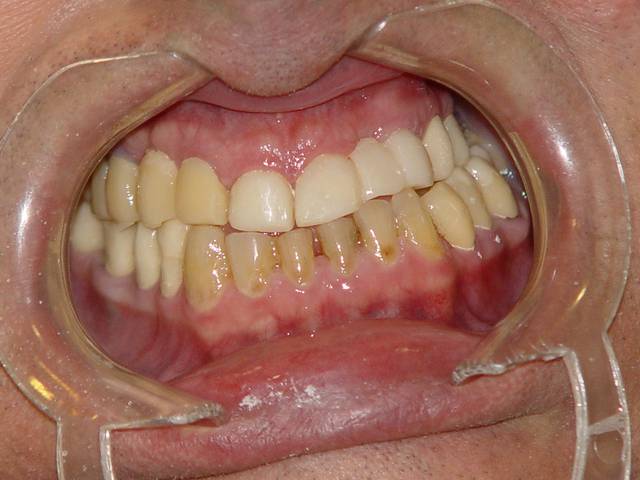

Cas terminé en décembre 2006, revu la semaine dernière, ce qui m'a donné envie de vous le montrer.

voilà les photos excusez moi d'en avoir doublé une, , quant à la dernière, c'est celle de la semaine dernière.